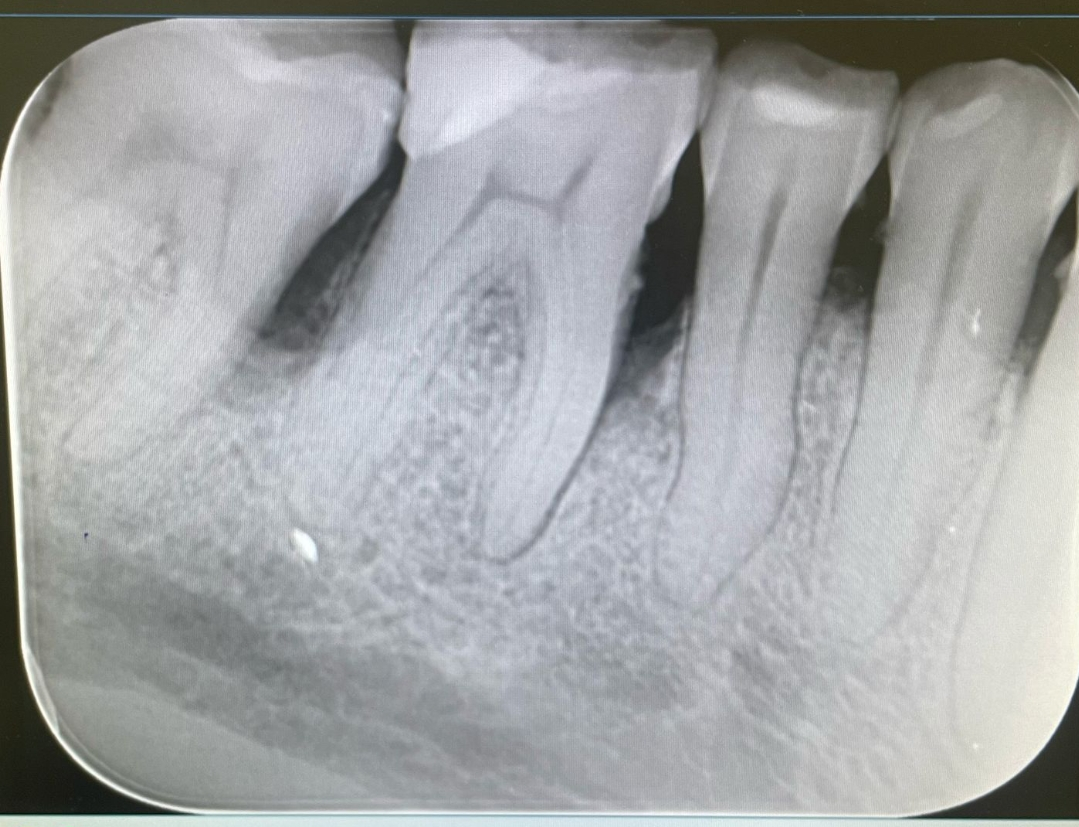

Как ви се струва този мъдрец (на снимката е зъбът вляво)? Дали има кариеси между мъдреца и седмия зъб (тези по-тъмните зони между двата зъба визирам)?

На 3D скенер (cbct) зъболекарят каза, че и а някаква костилка в основата на мъдреца, но според него тя бе бука проблемна, а се е формирала заедно с мъдреца. Каза, ако зъбът не ми причинява проблеми, че няма нужда да го вадя. Понякога усещам сякаш има "нещо" в зоната на седми и осми зъб, но съвсееем лека и тъпа болка (затова питам дали може да има скрит кариес), а и не е постоянно.

На мястото на шестия зъб ще има имплант. Около четвърти и пети зъб (с доста стари коронки са) има гранулом (на 3D скенера мисля, че тръгва от четвъртия зъб). Дали мога да отложа лечението на гранулома с няколко месеца без това да се отрази зле на импланта?🤔